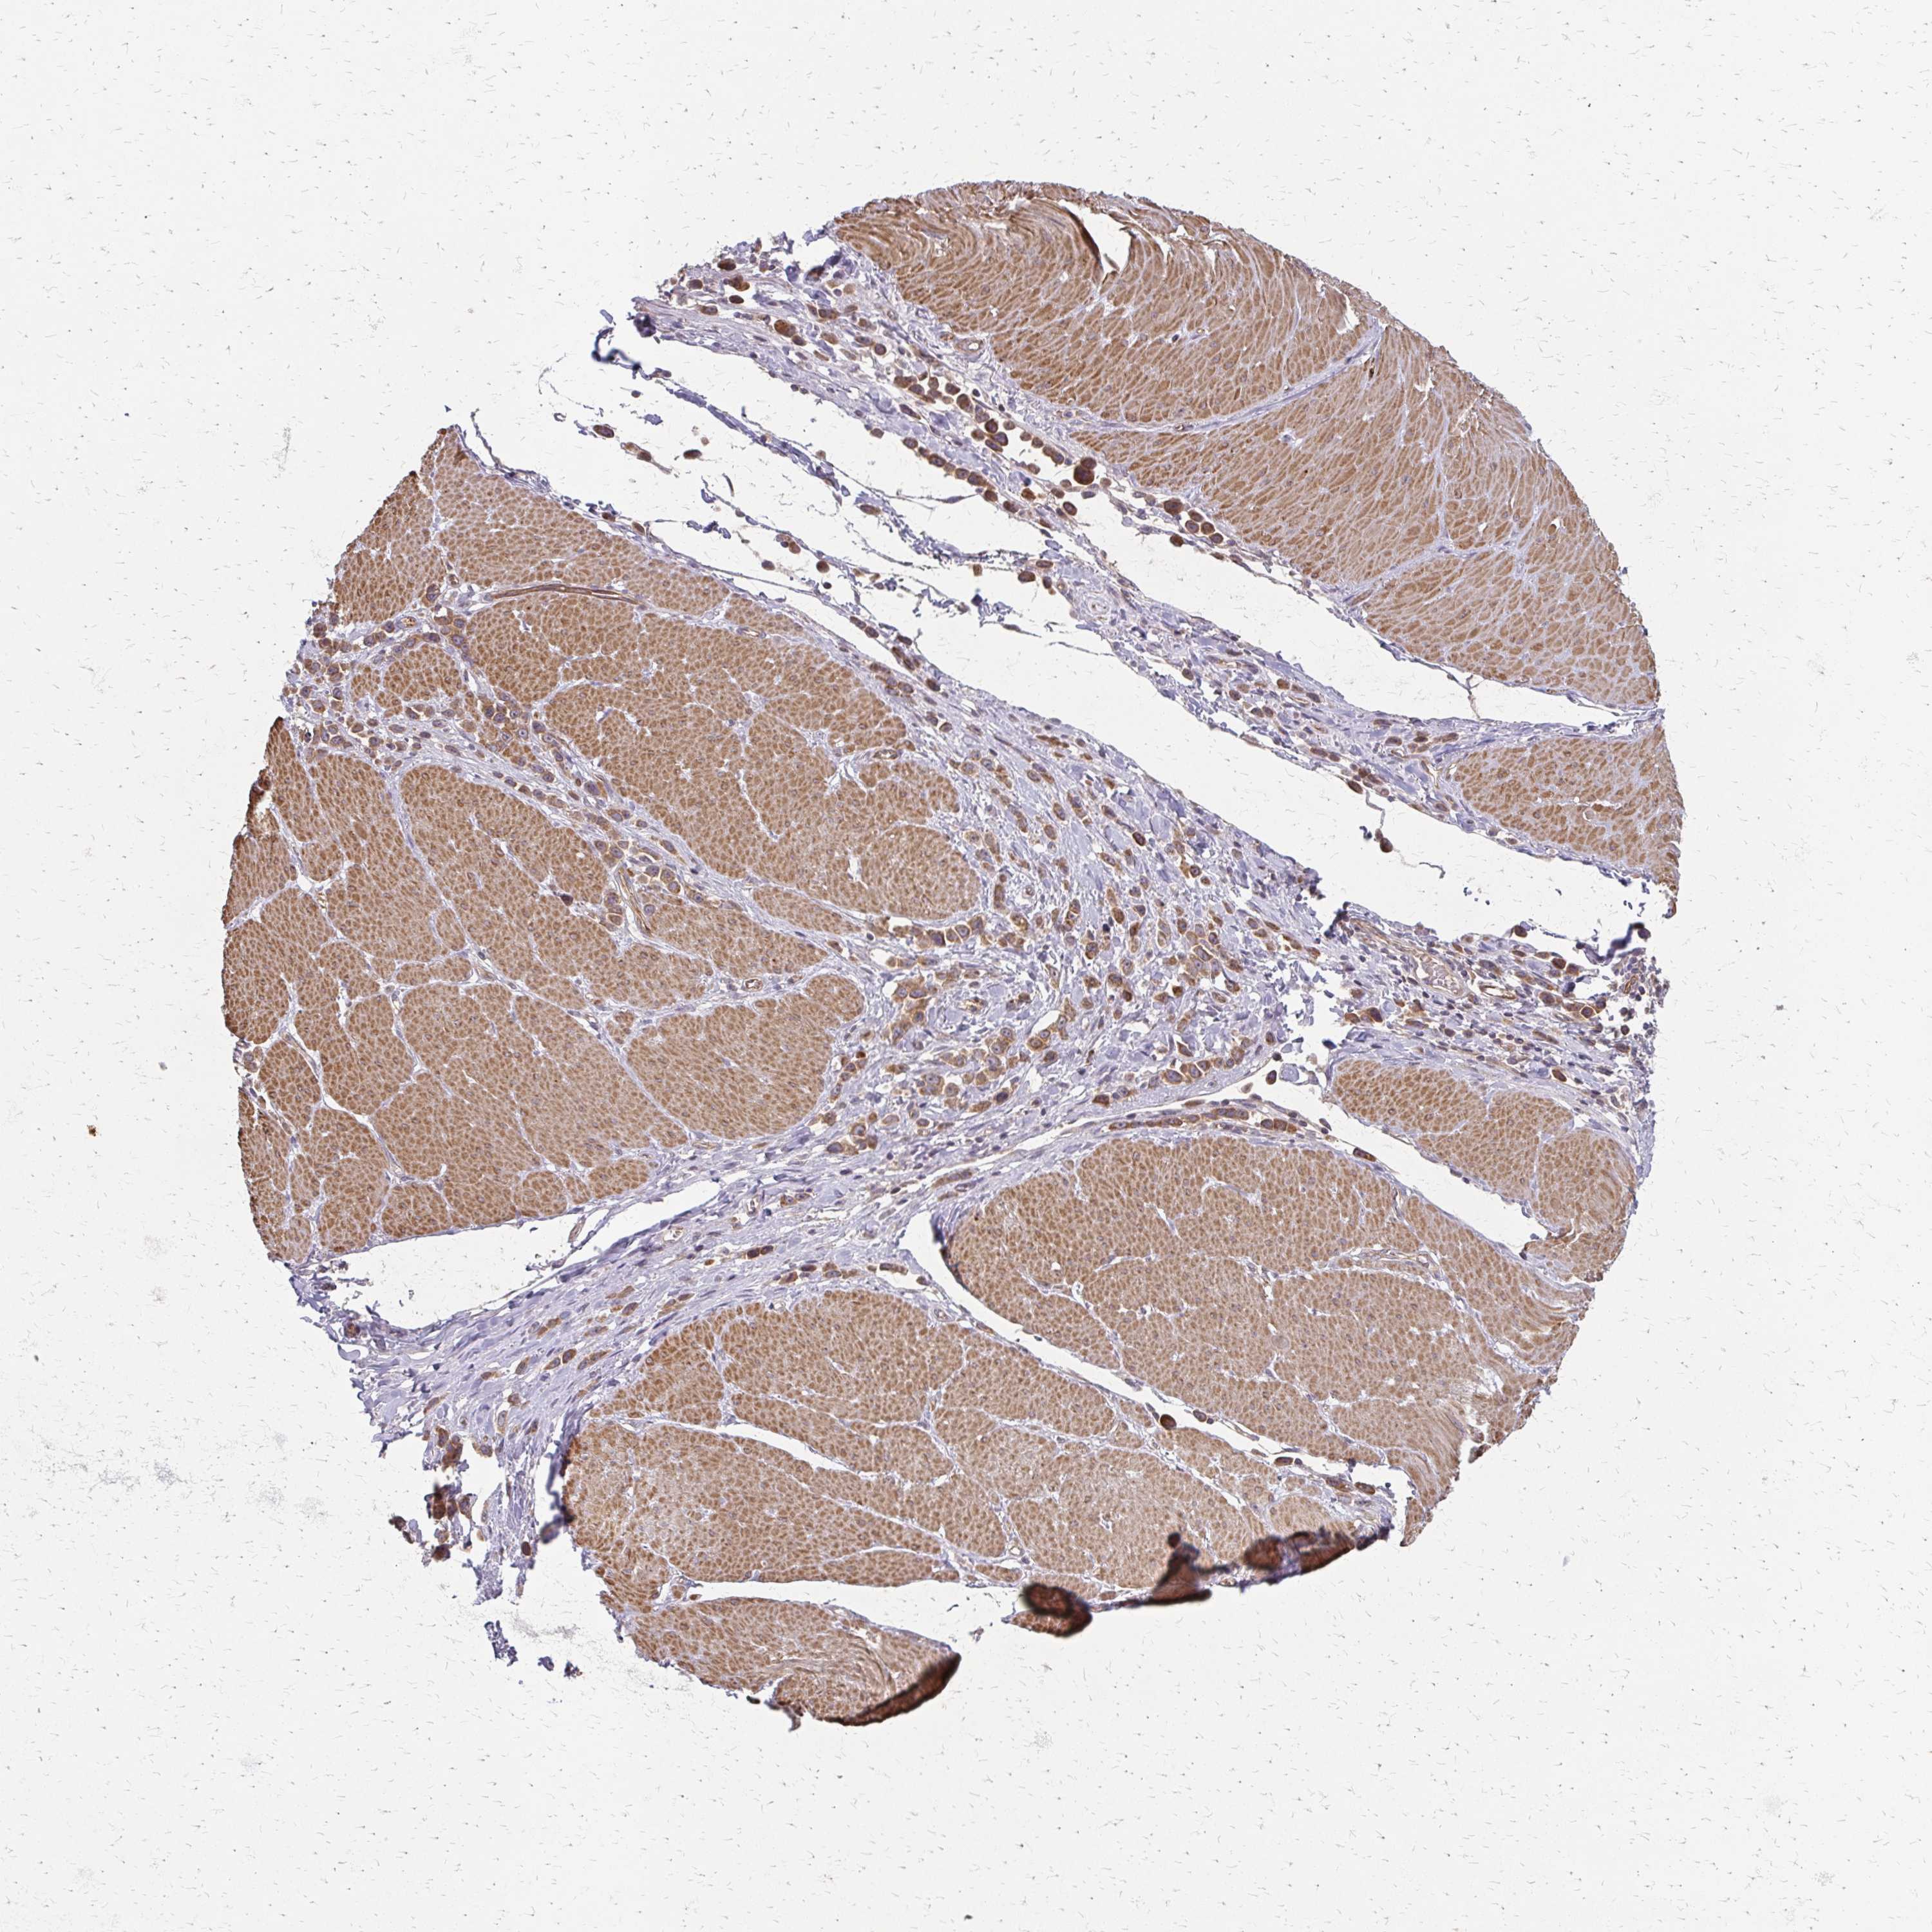

STOMACH CANCER - Protein expressioni

A mouse-over function shows sample information and annotation data. Click on an image to view it in a full screen mode. Samples can be filtered based on level of antibody staining by selecting one or several of the following categories: high, medium, low and not detected. The assay and annotation is described here.

Note that samples used for immunohistochemistry by the Human Protein Atlas do not correspond to samples in the TCGA dataset.

Antibody stainingi

Antibody staining in the annotated cell types in the current human tissue is reported as not detected, low, medium, or high, based on conventional immunohistochemistry profiling in selected tissues. This score is based on the combination of the staining intensity and fraction of stained cells.

Each image is clickable and will lead to virtual microscopy that enables deeper exploration of all samples and also displays staining intensity scores, fraction scores and subcellular localization as well as patient and tissue information for each sample.

Antibody HPA063945

Staining

High

Intensity

Strong

Quantity

>75%

Location

Nuclear

Adenocarcinoma, NOS